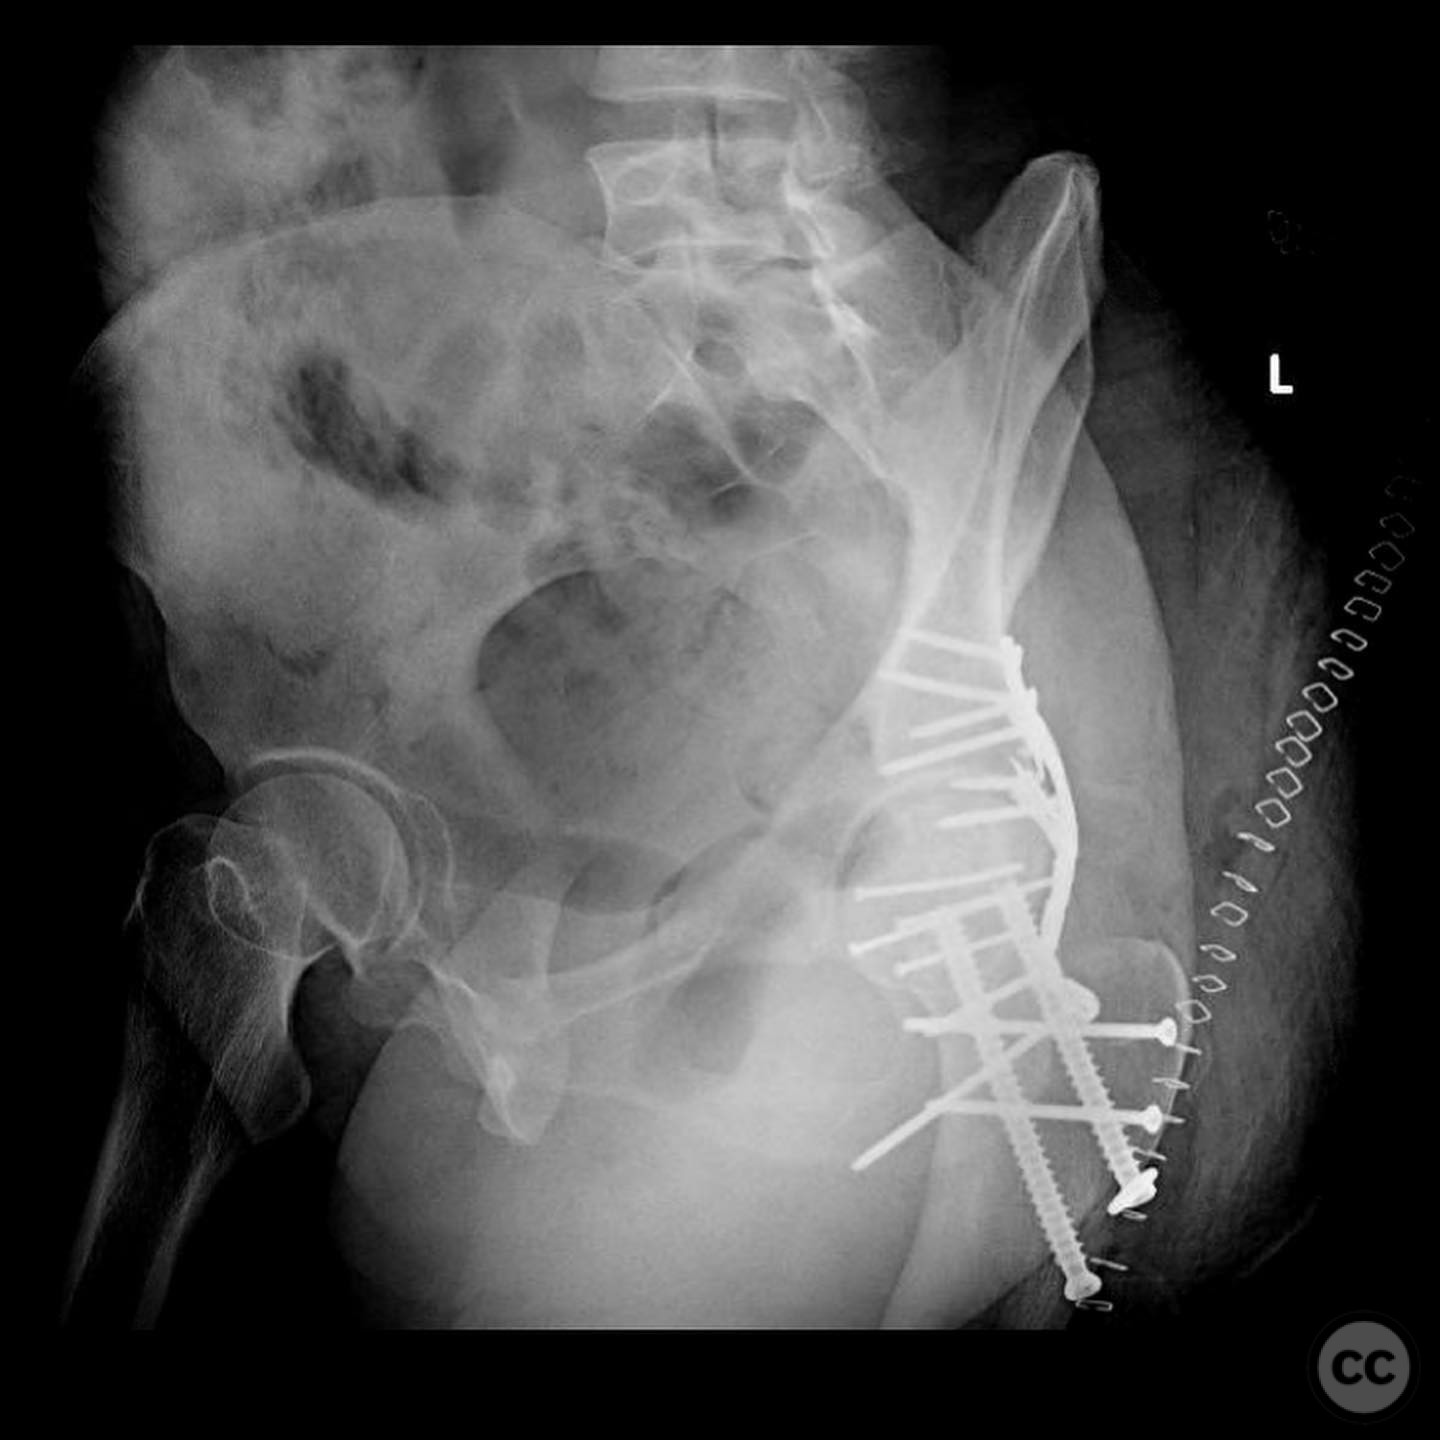

Pipkin IV Femoral Head Fracture with Posterior Wall Involvement and Femoral Neck Fracture.

Clinical and radiological findings:  A 33-year-old female involved in a motor vehicle collision presented with a posterior hip dislocation accompanied by a comminuted supra-foveal femoral head fracture, a cranial peripheral posterior wall fracture, and a non-displaced femoral neck fracture. The injury is associated with a risk of sciatic nerve palsy and avascular necrosis (AVN).

Preoperative Plan

Planning remarks:  The preoperative plan involved a Gibson approach with a trigastric slide osteotomy for anterior dislocation to address the femoral head fracture. The intention was to reconstruct the femoral head using a femoral head allograft due to a 20% pie slice defect. The posterior wall was to be addressed through capsulolabral repair with suture anchors and spring plates.